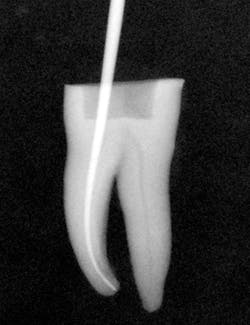

Figure 3: Radiograph showing master gutta-percha point fit to length.

I then use the Tango finishing instrument (double blue band on the latch head) in the same manner as described above. Always use the instrument wet. If you cannot achieve length, repeat the use of the Tango shaping instrument or use a 30/.04 SafeSider instrument to go to measurement. Confirm the Tango finishing instrument reaches the apical measurement. Move the instrument continuously against the canal walls until there is no resistance. I then fit the Tango-Endo gutta-percha point (figure 3). Figures 4 and 5 demonstrate the pre- and postop clinical radiograph.